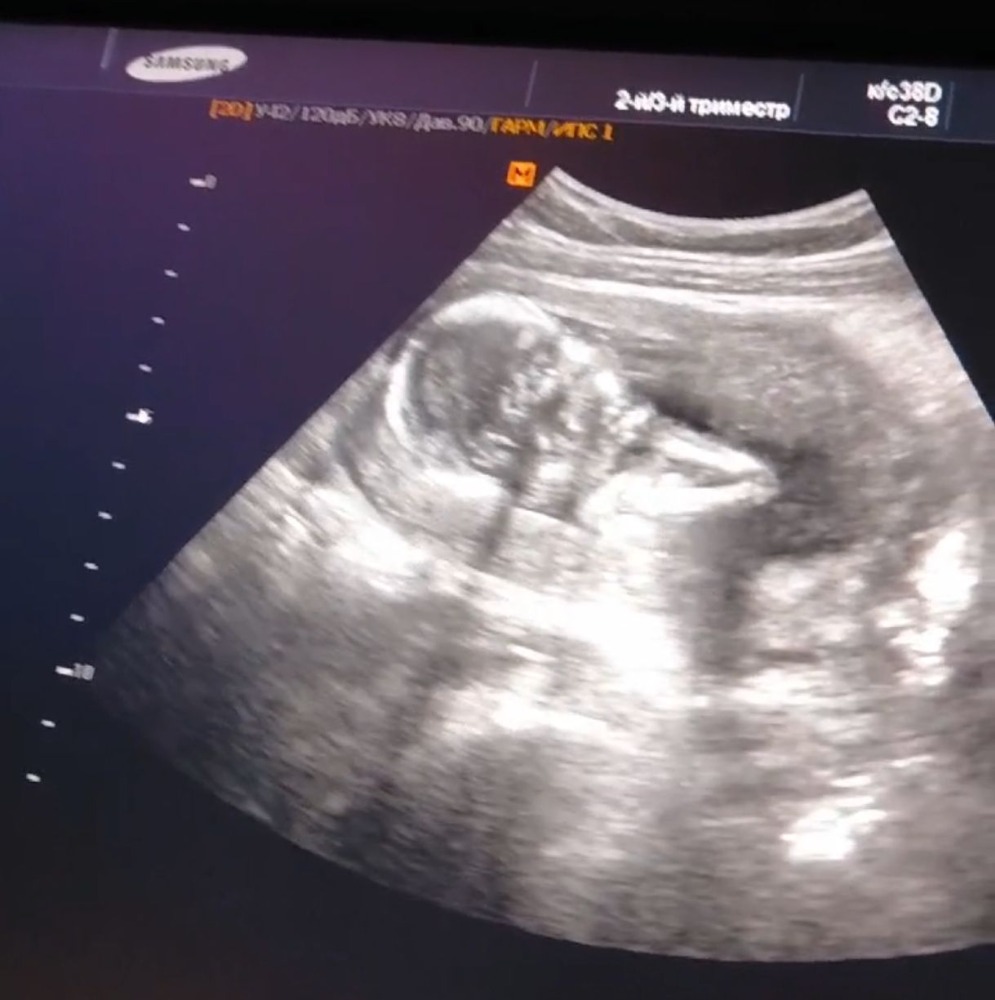

Узи 15 нед 4 дня

Это у вас 1 скрининг был ?

Крис, нет, первый был в 11,2 и в 12,1) это просто на узи ходила